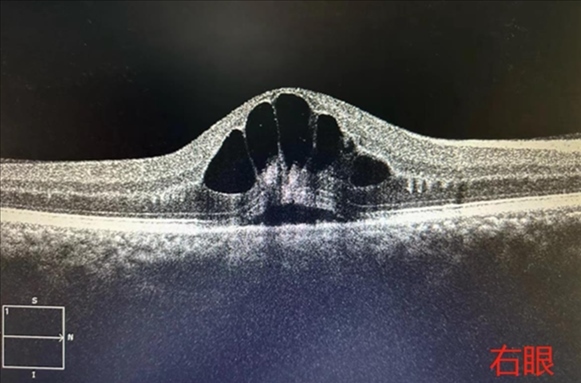

·男子胡吃海喝一周后眼底“長(zhǎng)出花瓣”,眼科專(zhuān)家提醒:假期應(yīng)健康飲食。